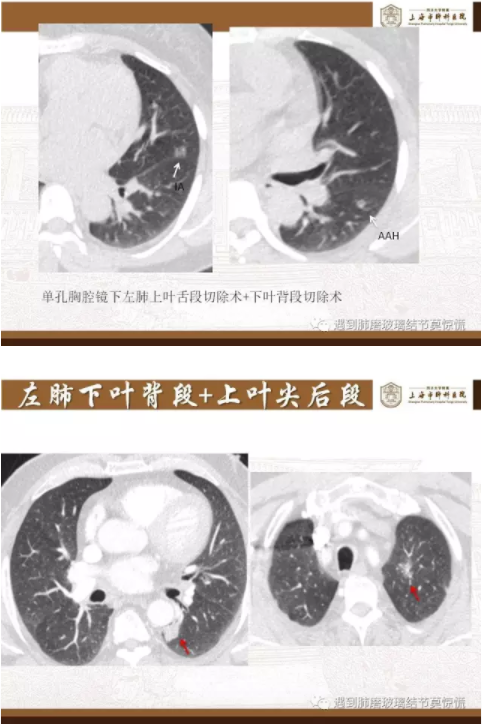

下面就我们的病例分析一下怎么进行肺段切除。

MIA= 微浸润腺癌   IA= 浸润性腺癌   AIS= 原位腺癌   AAH= 不典型腺瘤样增生